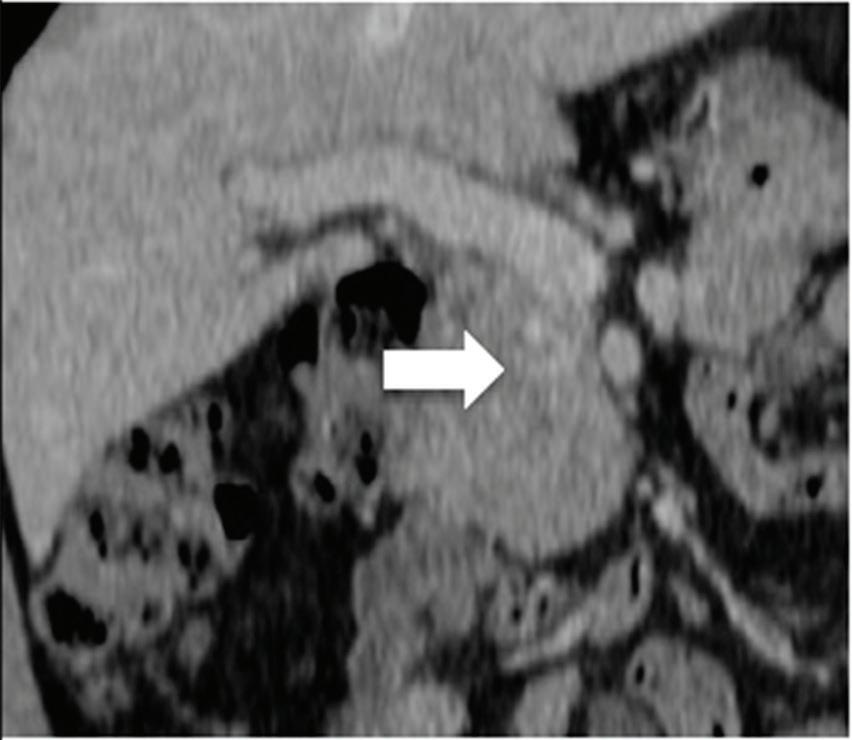

Multifocal HCC treated with sorafenib. (a) A small nodule (arrow) is barely seen on conventional axial CT image, acquired at late arterial phase after administration of 70 ml of contrast material (iodine concentration 350 mg/ml). (b) Monoenergetic 50 keV and (c) Z effective images improve the detection of this small nodule as well as allowing better evaluation of the peripheral solid component of both nodules seen in these images, with a precision comparable to that of (d) post contrast MR image.

A small isoattenuating pancreatic adenocarcinoma (arrow), (a) which tend to blend into normal parenchyma on conventional axial CT image, acquired at pancreatic parenchymal phase with administration of 70 ml of contrast material (iodine concentration 350 mg/ml). (b) Monoenergetic 50 keV and (c) Z effective images improve detection by increasing conspicuity and contrast between tumor and normal parenchyma.

Liver tumors. Use of low-monoenergetic images on late arterial phase improves the detection of hypervascular liver lesions (e.g., HCC in cirrhotic liver) (Figure 4).3,17,52,53 It also improves detection of hypovascular liver metastases on portal-venous-phase.54

Pancreatic tumors. Several studies have demonstrated an obvious advantage of DECT for detection and staging of pancreatic adenocarcinoma using the low-monoenergetic data sets (Figure 5), regardless of the timing of the acquisition applied (single venous phase,55 pancreatic parenchymal phase,56 single split bolus single acquisition57).